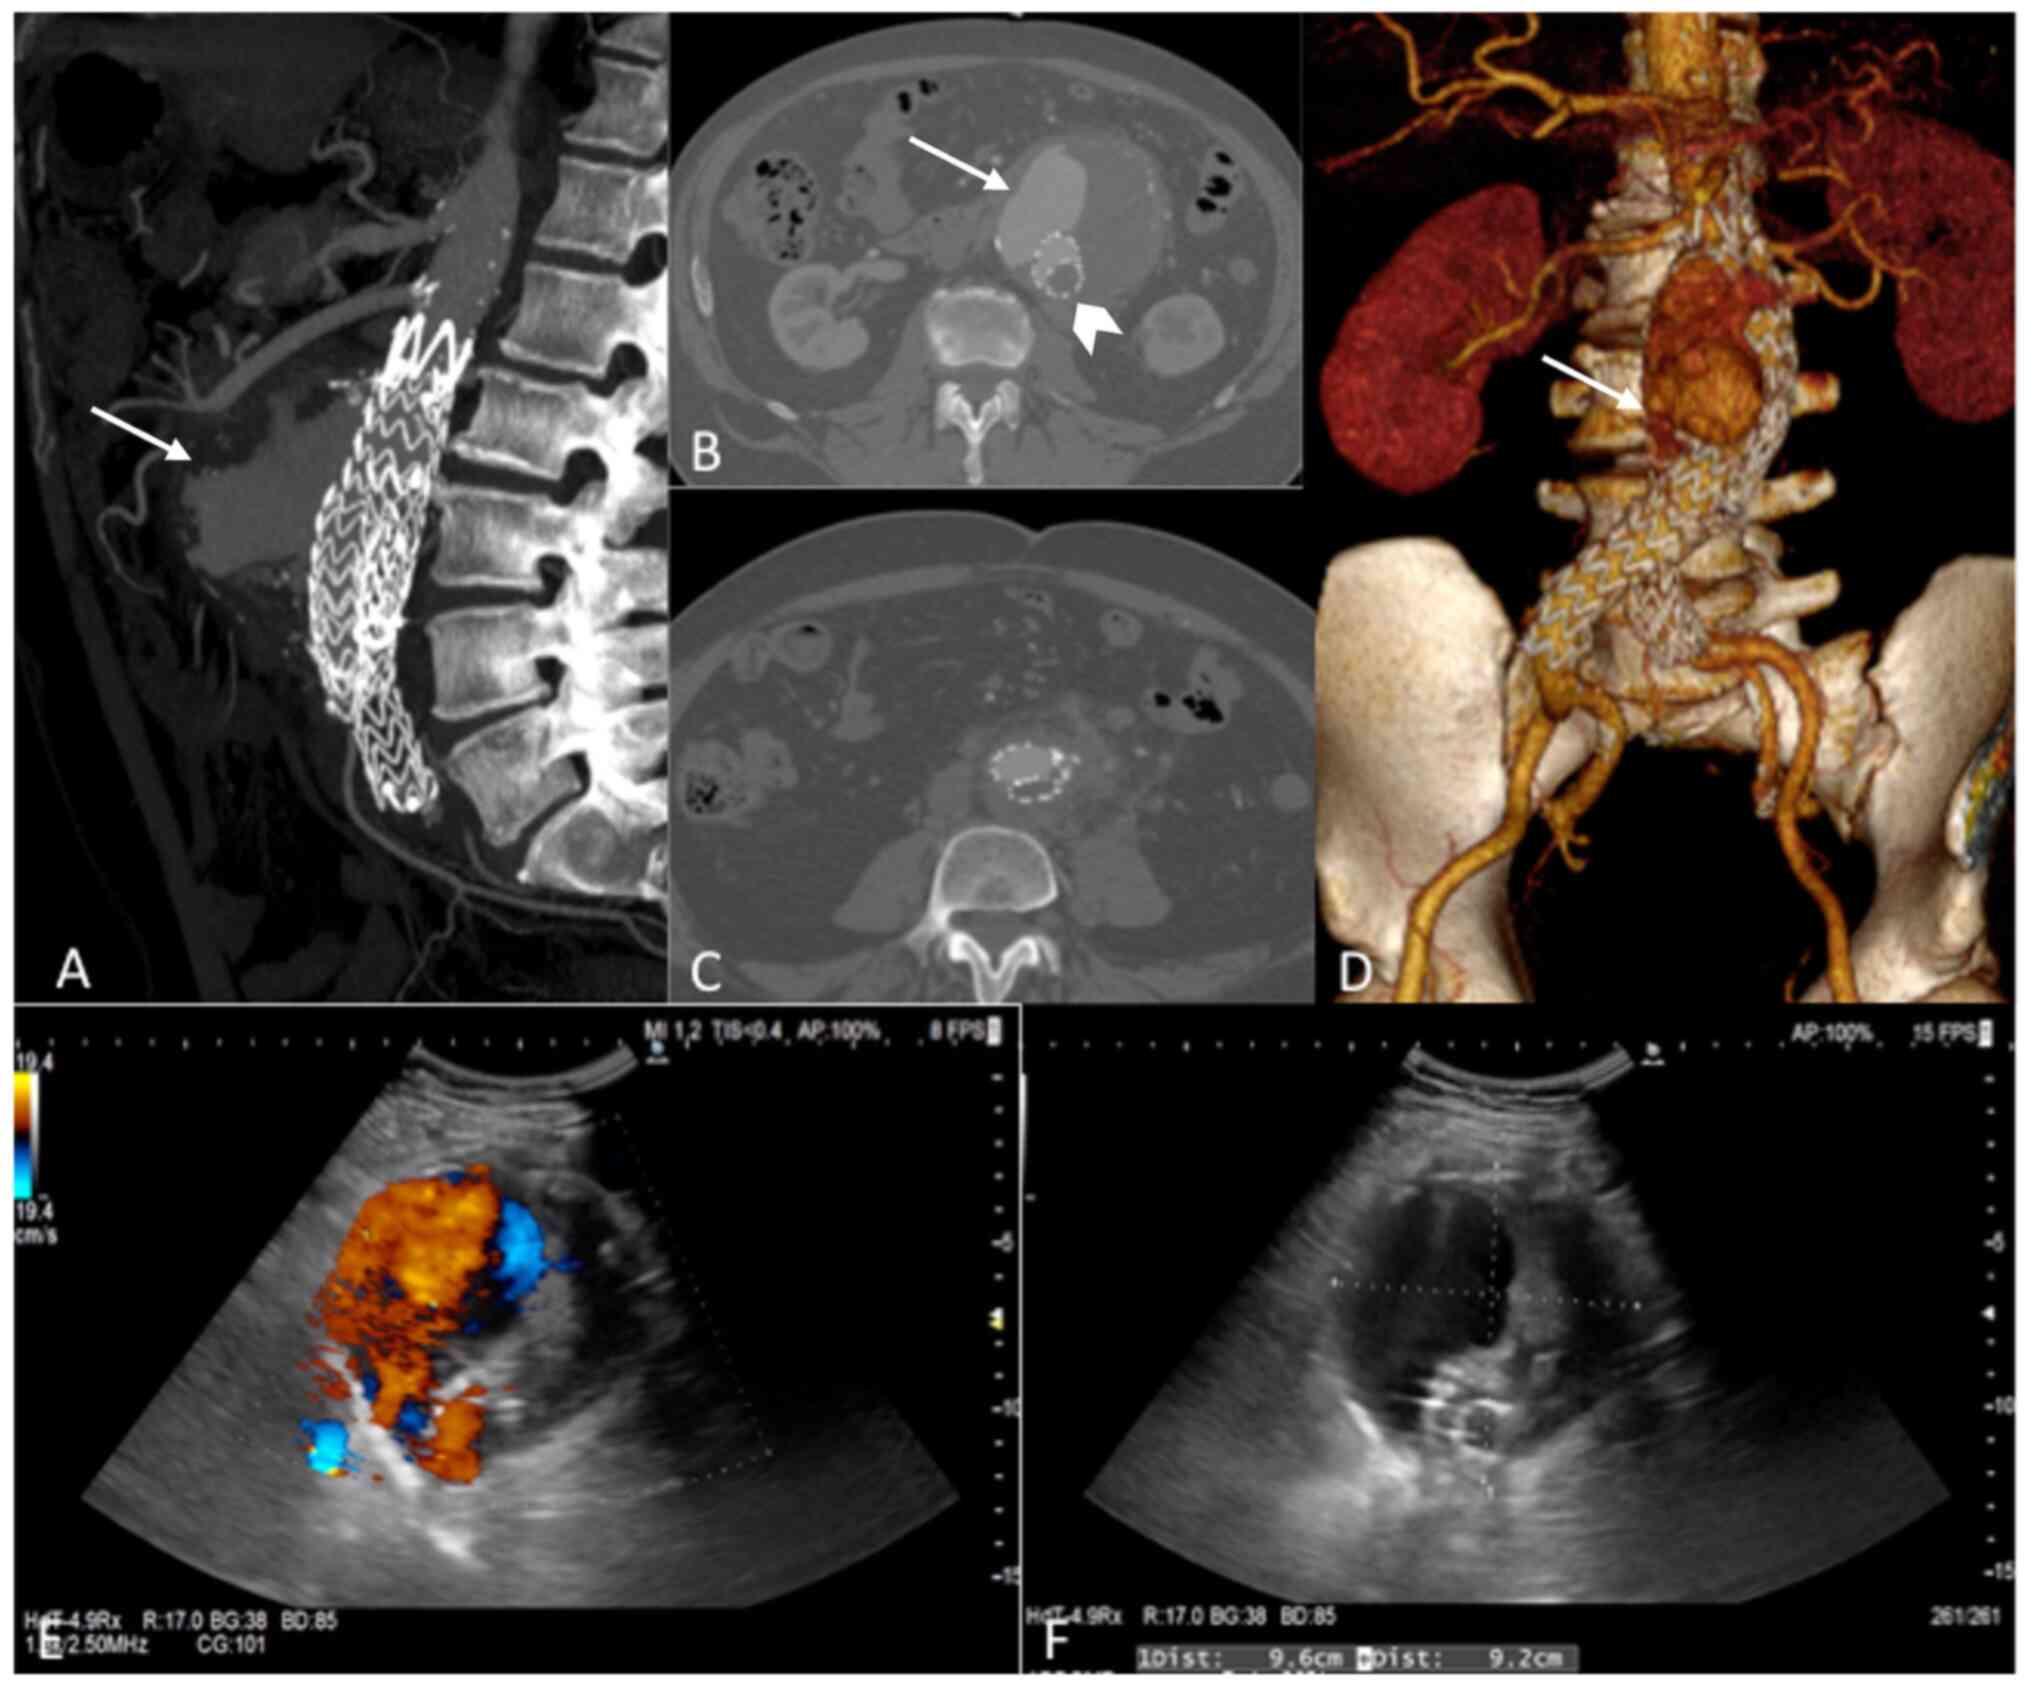

Subsequently, after a further 8 months, due to the presence of abdominal pain and persistent left calf claudication, the patient was admitted to our hospital ‘Campus Bio-Medico’ University of Rome (Rome, Italy) on February 2019, where color Doppler sonography and computed tomography angiography (CTA) revealed an abdominal aortic type Ia endoleak, with graft thrombotic occlusion and a maximum diameter of the aneurysm of 91 mm (Fig. 1A-F). Neither gas bubbles nor any obvious indications of graft infection were present. Similarly, laboratory investigations failed to reveal any abnormalities, with the exception of the white blood cell count (13,800 cells/µl), a C reactive protein concentration of 2.1 mg/dl (normal value <0.5 mg/dl), and a creatinine reading of 1.3 mg/dl, albeit without clinical signs of systemic infection.

Figure 1

Preoperative computed tomography angiography (CTA) showing (A-D) perfusion of the sac due to type Ia endoleak (white arrows) and left limb occlusion (arrowhead). (E and F) Preoperative duplex ultrasound also showing the huge aneurysm with high-flow endoleak.